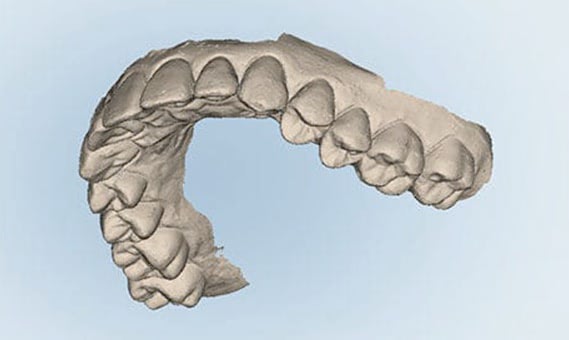

口腔内3Dスキャナー

3Dスキャナーとは、詰め物や被せ物の型取りの際に、お口の形を読み取る小型カメラです。従来はお口を大きく開けたままガムのような印象材で型取りをしていましたが、3Dスキャナーがあれば、たった数分お口の中にカメラを向けるだけで済みます。印象材をお口に詰め込んだ時のように、吐き気を感じることもありません。